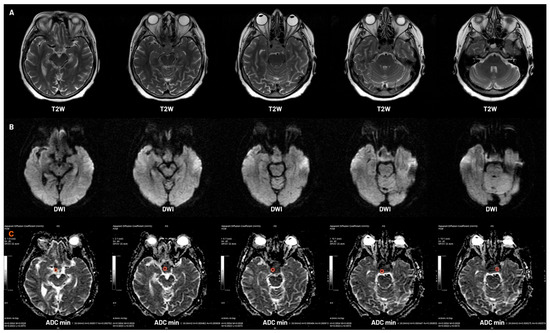

- Korbecki, A.; Wagel, J.; Zacharzewska-Gondek, A.; Gewald, M.; Korbecka, J.; Sobański, M.; Kacała, A.; Zdanowicz-Ratajczyk, A.; Kaczorowski, M.; Hałoń, A.; et al. Role of Diffusion-Weighted Imaging in the Diagnosis of Pituitary Region Tumors. Neuroradiology 2025, 67, 437–447. [Google Scholar] [CrossRef]